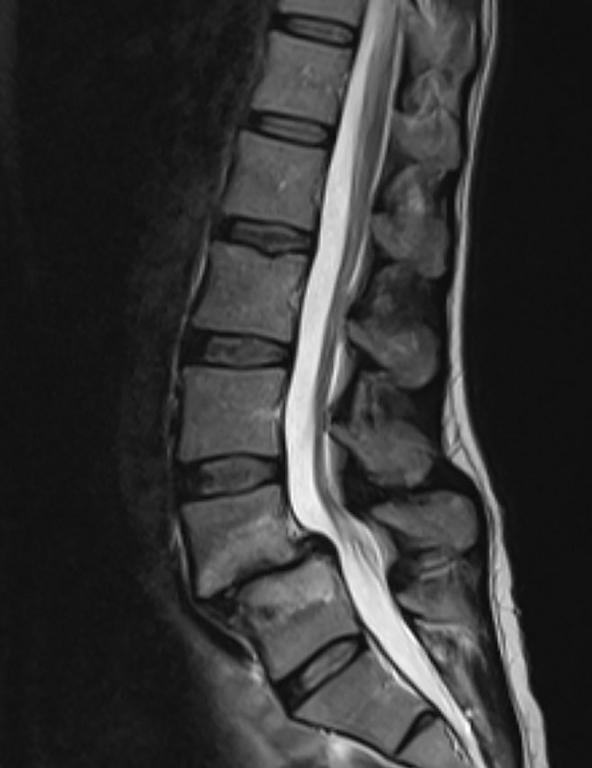

Dit artikel is het laatste deel van het drieluik over het ‘zware’ leven van de lumbale disci intervertebrales. In deel 1­ (editie ­2020-3­ van­ Physios) ­zijn­ de­ bouw, ­functie ­en ­de­ bloed-­ en ­zenuwvoorziening ­van ­de ­lumbale­ discus beschreven­ en ­is ­het ­verschil ­tussen discusdegeneratie­ en­ discusveroudering­ belicht.­ Deel­ 2­ (editie­ 2021-4­ vanPhysios) is ingegaan op verschillende aspecten van discusdegeneratie. Er zijn morfologische kenmerken van discusdegeneratie besproken, het veranderde mechanische gedrag van een discus met discusdegeneratie is beschreven, en besproken is hoe zowel mechanische als biologische factoren een rol spelen in de progressie van discusdegeneratie. Deel ­3­ staat ­eveneens ­in­ het­ teken­ van­ discusdegeneratie.­ Het ­artikel­ start­ met­ de ­oorzaken­ van het­ ontstaan ­van discusdegeneratie. Hierbij spelen niet mechanische factoren de belangrijkste rol, zoals vaak gedacht wordt, maar juist genetische factoren. Al jaren is bekend dat het op individueel niveau niet mogelijk is om aan de hand van de ernst van discusdegeneratie, vastgesteld via beeldvorming, te voorspellen of de persoon asymptomatisch (zonder lage rugpijn) of symptomatisch (met lage rugpijn) is. Maar wat maakt dan wel het verschil? Na een poging tot een antwoord op deze vraag sluit het artikel af met de beschrijving van de fysiotherapeutische behandeling van een patiënt met lage rugpijn op basis van discusdegeneratie.